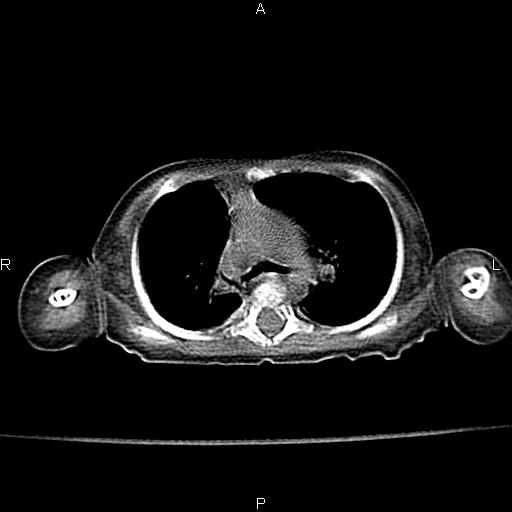

以下是引用aa13877358820在2010-7-26 12:35:00的发言:[br]男性,三个月,卧位胸片,咳嗽、气促、发热14天,两肺闻及细小水泡音。[br]

以下是引用jsdtd在2010-7-26 14:42:00的发言:[br]胸腺呈帆状,体位所致,没事。